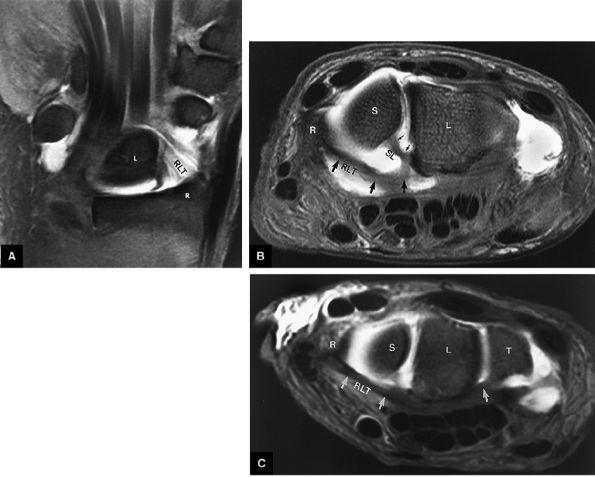

FIGURE 10.60 ● (A) A coronal section of the hand shows the joints of the carpal region. The thumb and little finger are anterior to the plane of section. (B) Coronal FS PD FSE image demonstrating the membranous components of the scapholunate (SL) and lunotriquetral (LT) ligaments. The central disc of the TFC is identified. (C) Complete osseous lunotriquetral coalitions are fibrous, cartilaginous, or osseous. Osseous coalitions may be incomplete or complete.

FIGURE 10.63 ● The long radiolunate or radiolunotriquetral (RLT) ligament. (A) The RLT ligament is divided into a radiolunate ligament and lunotriquetral component. The RLT ligament functions as a volar sling for the lunate. L, lunate; R, radius. Volar FS coronal T1-weighted arthrogram. FS axial T1-weighted arthrograms obtained at the level of the proximal (B) and distal (C) aspects of the radial styloid show the volar course of the RLT ligament (large arrows) from the radial styloid (R) inserting into the lunate (L) and blending with the volar portion of the lunotriquetral interosseus ligament. The lunate attachment of the scapholunate interosseous ligament volar fibers is deep to the lunate attachment of the RLT ligament (B). S, scaphoid; T, triquetrum; SL, scapholunate ligament.